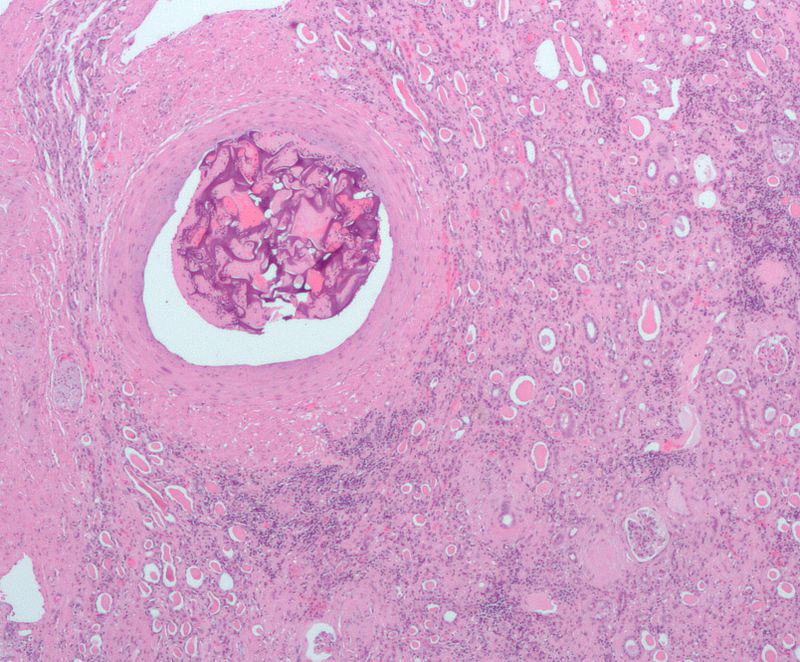

Angiomyolipoma

Angiomyolipoma is a disorder where benign kidney tumors develop.

Angiomyolipoma a tumor made up of blood vessels, smooth muscle, and adipose tissue.

Tuberous sclerosis is associated with angiomyolipoma.